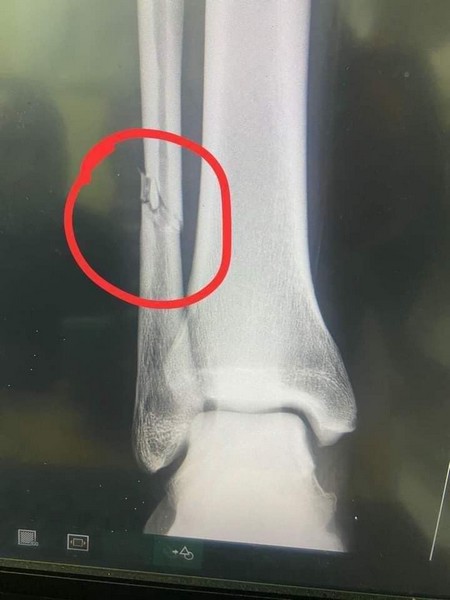

Rimsport - Après avoir subi un tacle violent d'undéfenseur de Simba Sc, dimanche (13 mars) en match comptant pour la quatrième journée de la Coupe de la Confédération - CAF, Adama Ba a révélé sur les réseaux sociaux souffrir d'une fracture du péroné de la jambe droite.

Un tacle extrêmement violent au tibia du joueur tanzanien, et Adama Ba qui crie de douleur. Les images font froid dans le dos. L'attaquant mauritanien de RS Berkane, revenu au meilleur de sa forme, après sa retraite internationale a été sévèrement blessé.